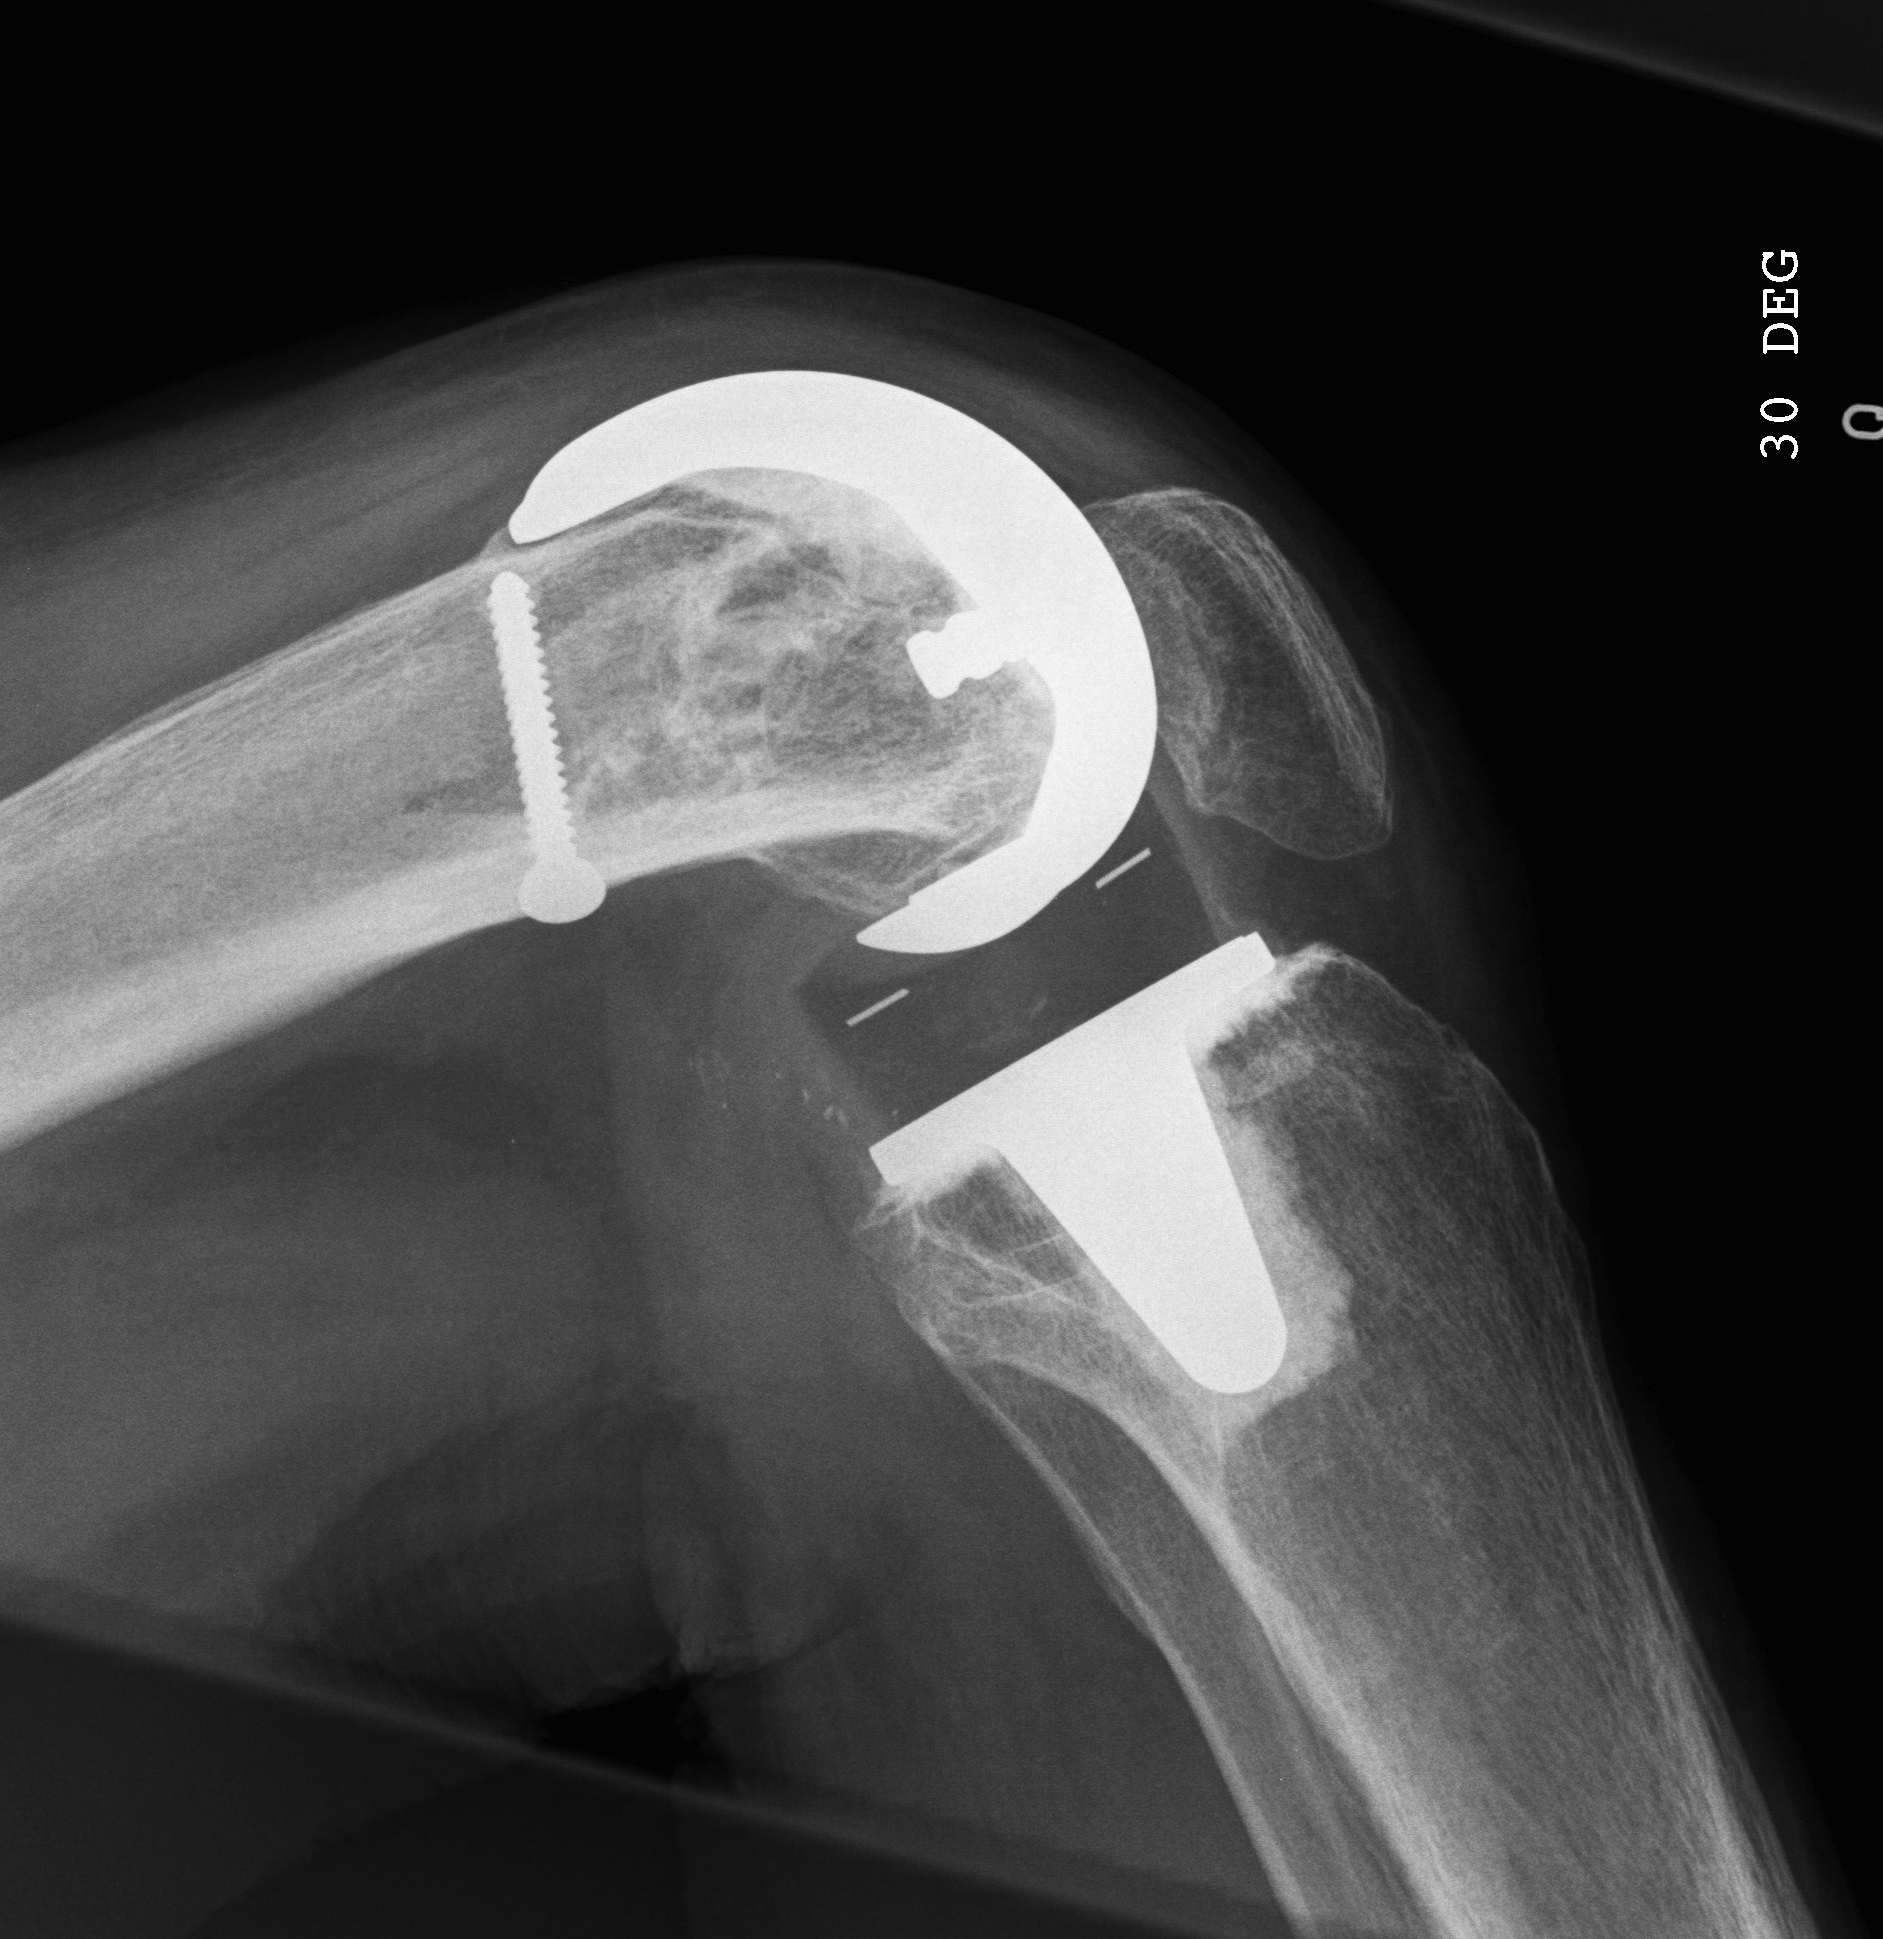

1.  Lateral locking plate

TKR Periprosthetic Fracture Minimall Dislplaced CTTKR Periprosthetic Fracture Locking Plate APTKR Periprosthetic Fracture Locking Plate Lateral

Technique

Minimally invasive technique

- may need unicortical screws distally